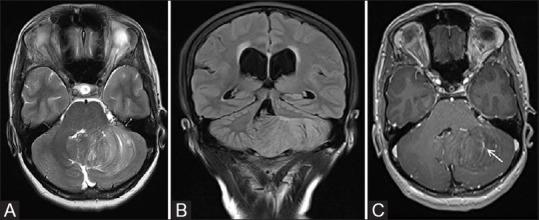

Phakomatoses or Neurocutaneous syndromes are a heterogeneous group of disorders and have variable inheritance pattern. Currently, more than 30 entities are included in this group. These disorders primarily affect the central nervous system; however, skin, viscera, and other connective tissues can also be involved with variable clinical presentation. We will describe and illustrate the various radiological findings of the common entities through the iconography of the cases presented to our department.

phakomatoses或神经皮肤综合征是一组异质性疾病,具有可变的遗传模式。目前,该组包括30多种疾病。这些疾病主要影响中枢神经系统;然而,皮肤、内脏和其他结缔组织也可能受累,临床表现各异。我们将通过提交至我科病例的影像学表现来描述和说明常见疾病的各种放射学表现。